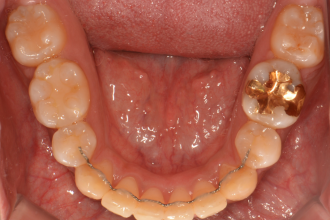

치아교정

굿프렌즈 치과 임상 케이스